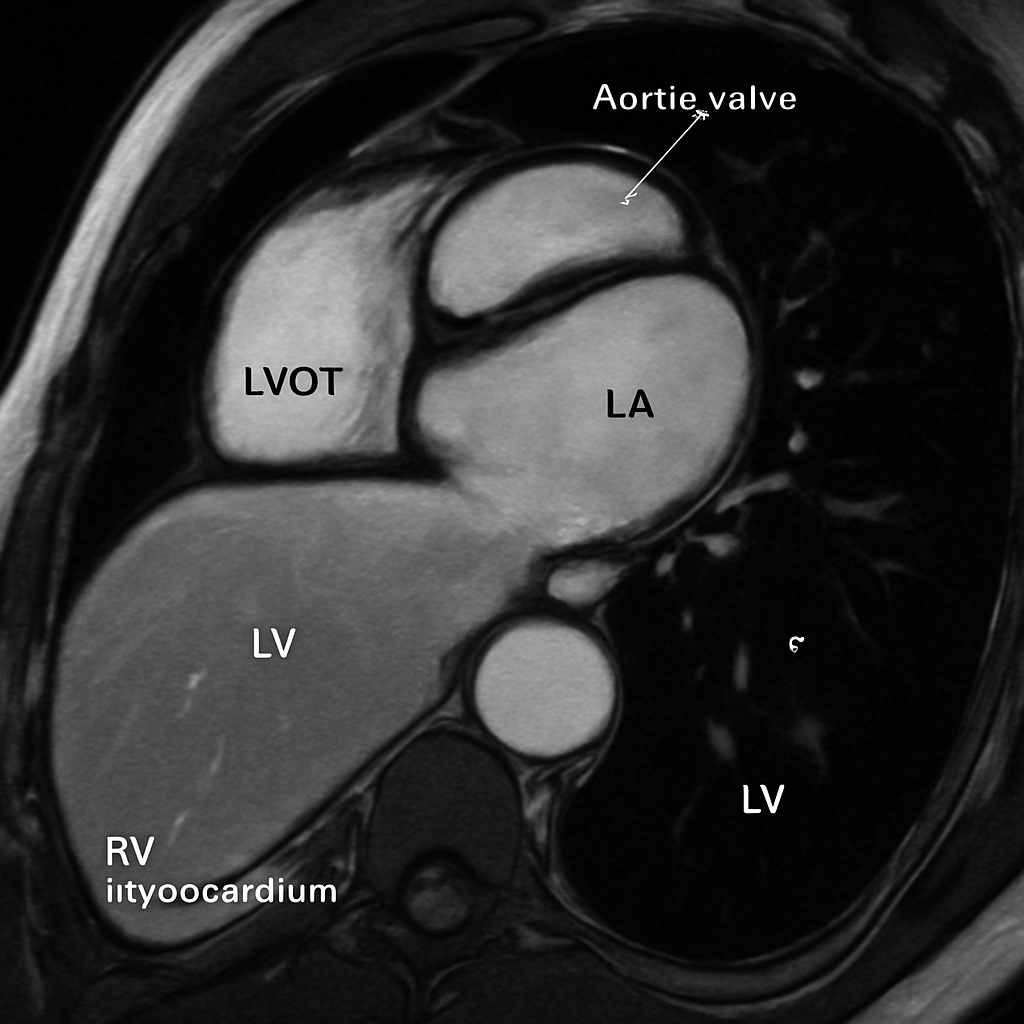

MRI — Three-Chamber / LVOT View

Cardiac MRI three-chamber view showing the left ventricular outflow tract (LVOT), aortic valve, ascending aorta, LV, and LA. SSFP bright-blood.

Ssfp Three Chamber

bSSFP cine, three-chamber / LVOT view. Show aortic valve, ascending aorta, LV, LA.